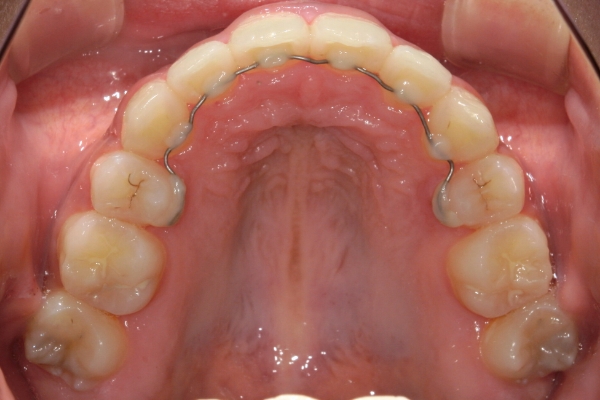

歯の移動を終えると、矯正装置をすべて取り外します。装置の撤去後は、後戻りを防止して歯並びを安定させるために、保定装置(リテーナー)を使っていただきます。 保定開始後すぐは1~3か月毎、歯列の後戻りが少なくなってからは3~6か月毎にご来院いただき、噛み合わせと保定装置の状態をチェックします。 保定期間の長さは治療内容にもよって変わりますが、一般的には矯正治療に要した期間と同じ程度必要になることが多いです。

BEFORE

治療前

PROCESS

半年

AFTER

治療後

上顎前歯が1 cm近く前方に出ており、叢生を改善しつつ前歯を大きく引っ込めるために上下顎小臼歯の抜歯が必要と診断しました。治療では奥歯の噛み合わせのズレも整え、治療後は前歯でも奥歯でも食べ物が噛みやすくなったと、患者さまに非常に満足していただけました。